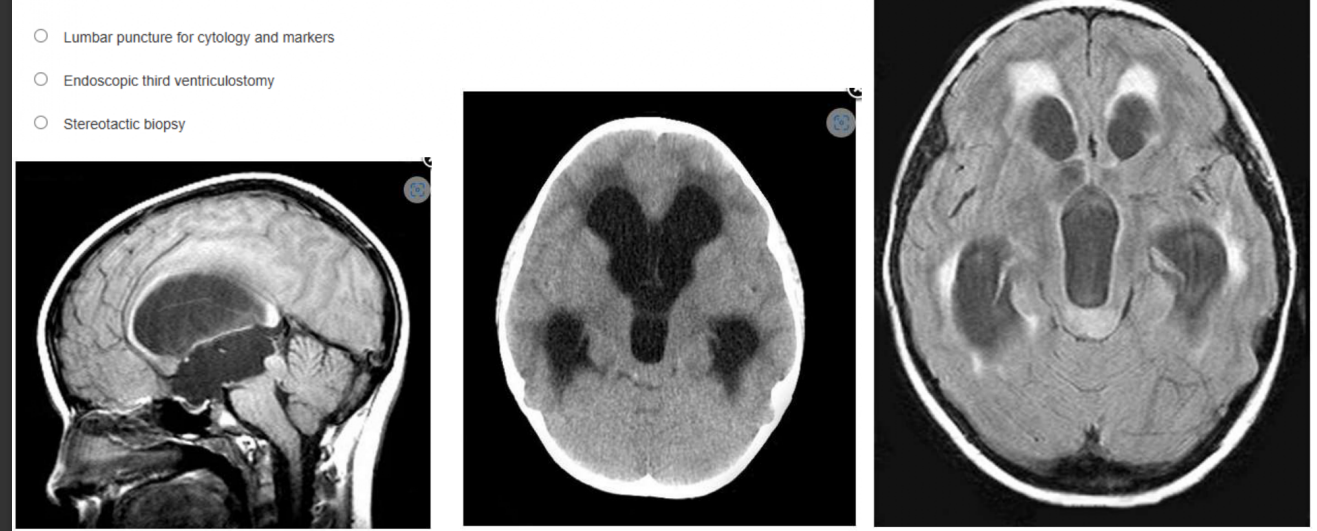

A 9 year-old girl visits her optometrist because of a 1-month progressive history of blurry vision and headaches. The optometrist notes

papilledema. Imaging is obtained. What course of action is indicated?

a. Conformal radiation therapy

b. LP shunt insertion

c. Lumbar puncture for cytology and markers

d. Endoscopic third ventriculostomy

e. Stereotactic biopsy

Endoscopic third ventriculostomy